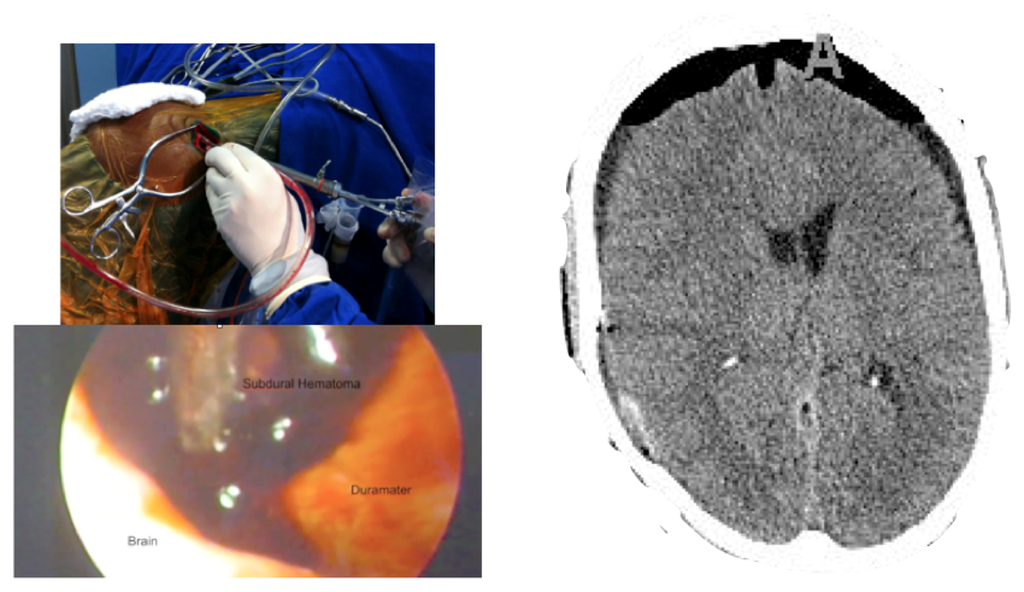

Case 2-Subdural Hematoma (See Figures 3 and 4 for the details)

A male patient of 44 years old was brought to the emergency department by relatives after falling from a height of 2 m. As the patient was well after the fall, he did not seek medical attention immediately. When he was admitted to the emergency room he presented GCS of 14 with left hemiparesis with muscle strength grade IV. The CT scan showed a subacute subdural hematoma extending over the entire convexity of the right brain. Therefore, he was promptly sent to the operating room. Upon completion of the 3D analysis it was opted for an endoscopic treatment of hematoma by a burr-hole positioned adjacent to the hematoma. The surgery was performed with no complications, and total resection was achieved. The patient had an excellent recovery, reversing the preoperative deficits. He was discharged four days after hospital admission.

Only three patients underwent surgery with the diagnosis of subdural hematoma, both acute (two patients), and subacute (one patient). All patients had lesions that extended all over the brain convexity with volumes ranging from 27 to 40 mL. All patients underwent an endoscopic resection through a burr-hole of 2 cm in diameter. Through the burr-hole, the neuroendoscope and another instrument (bipolar or aspirator) were introduced. The location of the bur-hole was calculated using the 3D model made immediately before surgery. The idea was place it at the periphery of the hematoma so that the aspirator and the endoscope could be inserted adjacent to the hematoma. This strategy allowed the complete resection of all hematomas without complications. All patients had a good outcome in view of the gravity that represents a subdural hematoma.